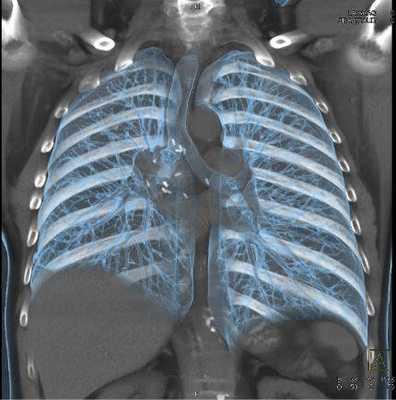

Используя метод объемного рендеринга, мы получили изображения грудной клетки: общая анатомия, пластическая анатомия, кости грудной клетки, мышцы грудной клетки, трахея и бронхи, легкие, сосуды грудного отдела, грудная аорта, легочные артерии, легочные вены и верхняя полая вена.

Мультиспиральная КТ грудной клетки, 3D-реконструкция